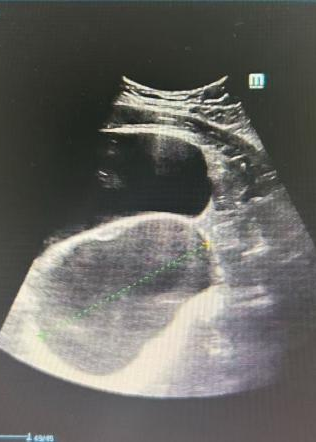

妇科彩超提示盆腔囊性占位

手术顺利开展。术中,任医生在患者右侧卵巢发现一枚约10cm×10cm×9cm的囊实性肿瘤(术后病理确诊为成熟性畸胎瘤),为最大限度保护卵巢功能,团队全程采用钝性分离手法,避免使用电凝器械,每一步操作都精准而轻柔。凭借娴熟的腹腔镜技术,手术过程顺利,出血极少,圆满实现了“微创治疗”与“功能保护”的双重目标。